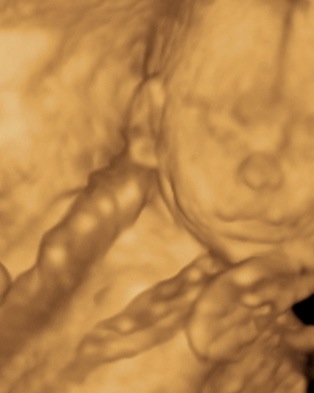

A 3D-s babafotok meg mindig lenyugoznek, nem birok betelni veluk. SZomoruan olvasom, hogy mennyi aprobb-nagyobb kellemetlensegetek van, de szerintem mindenki nagyon szuperul halad, ugyesek vagytok...le a kalappal foleg a dolgozok, vagy mar babasok elott! majd most teszek fel kepeket es is Azzurrarol, bar mar tobb, mint 5 hete keszultek, de ujabbak mar nem lesznek, es mivel kimaradtam abban az idoszakban, most potolom. Az tuti, hogy ezentul mindenkinek javasolni fogom a 4D-t ilyen koran is (22+1 hetesen voltunk), mert bar csimota ducibb volt az atlagnal es mar akkor volt rajta jo adagnyi izom (ez is a napi 1 l tej

), de egy sovanyabb baba is csodaszep szerintem...mindent el lehet mondani, csak azt nem, hogy csontkollekciok lennenek. Osszessegeben ugy nez ki, hogy ram hasonlit, de a szemoldokcsontja es a szaja az egy az egyben a parome...szerencsere...neki az sokkal szebb...remelem, haj-ugyben is ra ut majd